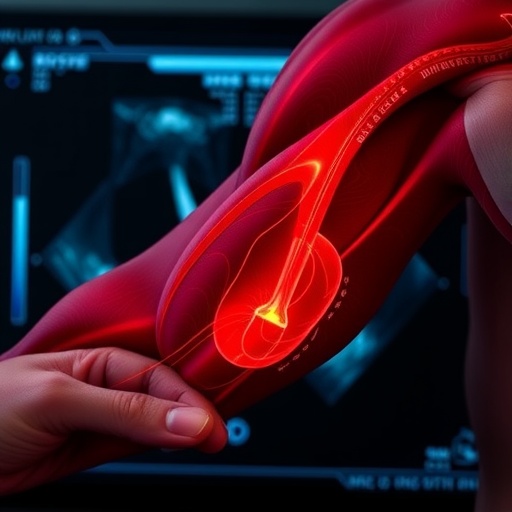

Ultrasound has gained popularity due to its non-invasive nature and ability to provide real-time images of muscle tissue. Unlike traditional imaging modalities like CT scans or MRIs, ultrasound offers a portable and cost-effective solution that can be performed at the bedside. These qualities make it particularly appealing for geriatric patients who often face mobility issues. However, despite its advantages, there remains a skepticism surrounding the reliability and predictive value of ultrasound in accurately diagnosing sarcopenia.

The authors argue that while ultrasound can visualize muscle architecture and assess cross-sectional area, its limitations must also be acknowledged. For example, factors such as hydration status, muscle quality, and the experience level of the operator can significantly affect results. This variability raises questions about the standardization of ultrasound techniques and the establishment of normative data across diverse populations. Until these standards are met, the effectiveness of ultrasound as a diagnostic tool remains uncertain.